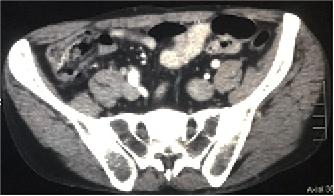

La presencia de uno o varios divertículos a nivel del apéndice cecal es poco frecuente con una incidencia evaluada en series quirúrgicas de 0.004 a 2.1%.1 El cuadro clínico no es específico y pueden cursar con dolor recurrente en la fosa iliaca derecha o bien presentarse como un cuadro de apendicitis aguda. Con frecuencia el cirujano realiza el diagnóstico preciso en el momento de la cirugía, o previamente por ultrasonido o por tomografía computarizada abdominal interpretada por un radiólogo experto.

Se expone un caso de diverticulosis apendicular en un paciente de 59 años de edad que se presentó con un cuadro abdominal agudo y que requirió intervención quirúrgica.

El estudio anatomopatológico reveló apendicitis aguda flegmonosa con diverticulosis apendicular (Figuras 1 y 2).

Figura 1: Tomografía computarizada de abdomen con signos de apendicitis aguda.